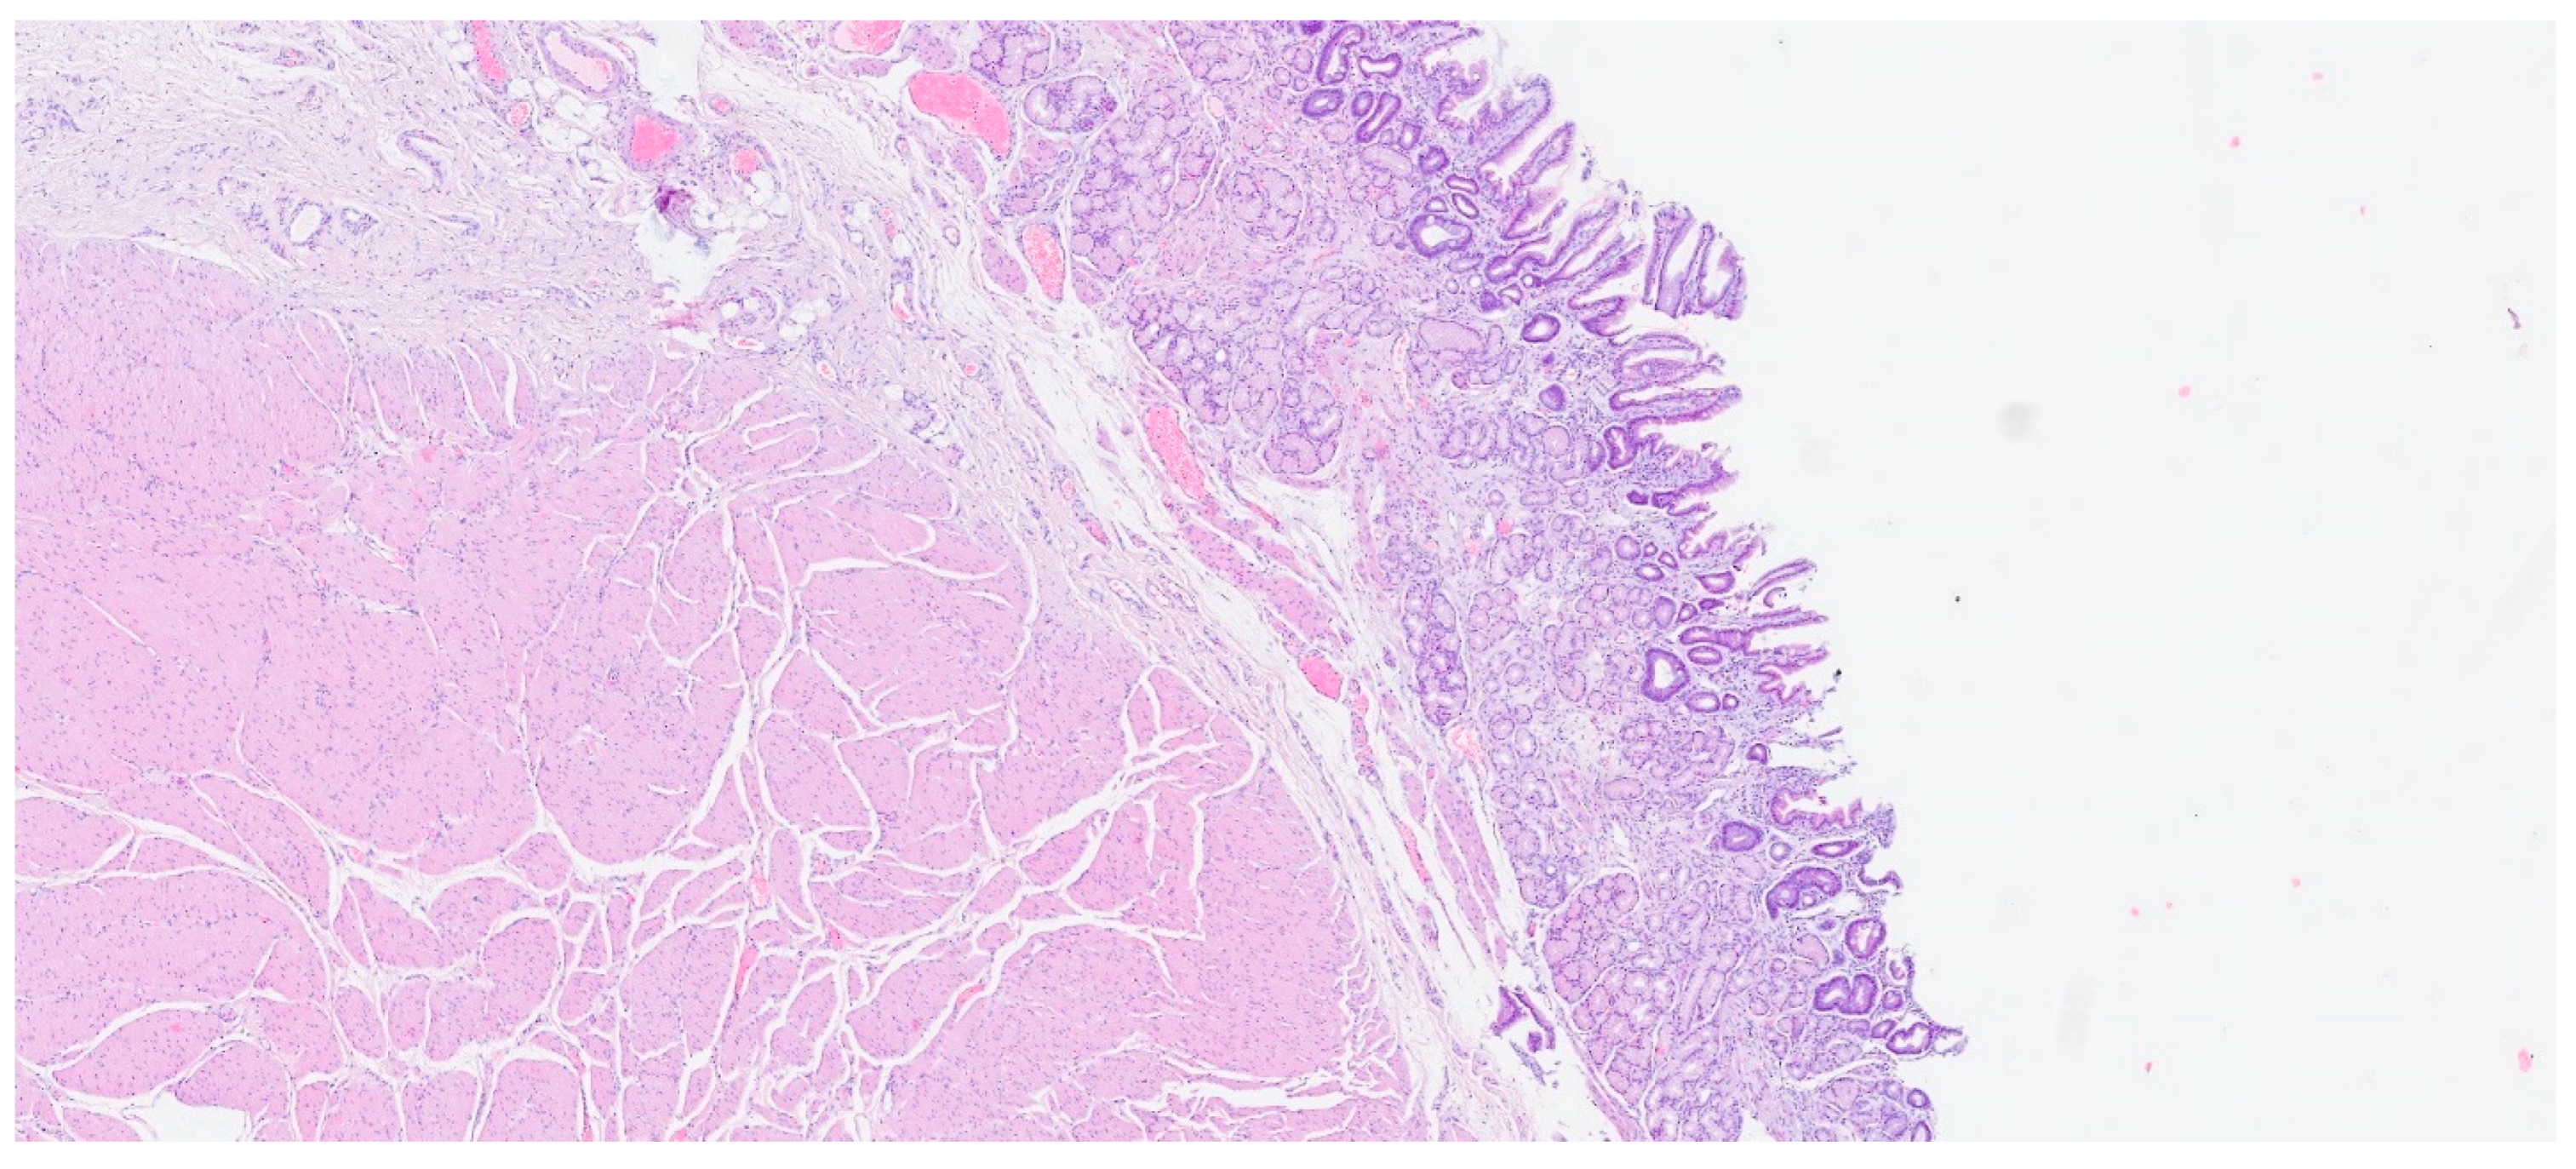

| Inflammatory fibroid polyp | Adults | Stomach | Incidental findings; some cases with abdominal pain, hemorrhage, or obstruction | Proliferation of spindle and stellate cells in haphazard distribution in the submucosa | CD34; PDGFRA |

| Plexiform fibromyxoma | Wide range of age | Antrum and pyloric region | Asymptomatic; some cases with ulceration | Bland spindle cells, supported by a myxoid/fibromyxoid/collagenous stroma and with a rich vascular network of thin-walled vessels in a multinodular pattern | SMA and, occasionally desmin positive. ALK, CD34, keratins, KIT, and DOG1 are negative |